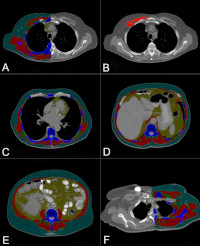

Automated Body Composition Measurement and Outcomes

• Improving the value of imaging in chronic disease evaluation by "opportunistically" quantifying patterns of muscle loss, fat loss, and paradoxical relationships between subtypes of obesity and survival using CT imaging.

• Two funded grants and >10 coauthored peer-reviewed manuscripts showed body composition is an independent predictor for outcomes of aortic disease, severe heart failure, non-Hodgkins lymphoma, breast cancer.